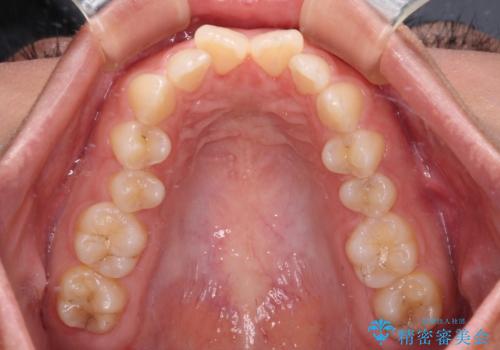

- 上の前歯が前方に飛び出していることを気にして来院された患者様です。

奥歯の咬み合わせをチェックすると、上顎歯列が相対的に前方に位置しているため、補助装置を用いて上顎歯列を確実に後方に移動させ、インビザラインで歯列を整えて行くこととしました。